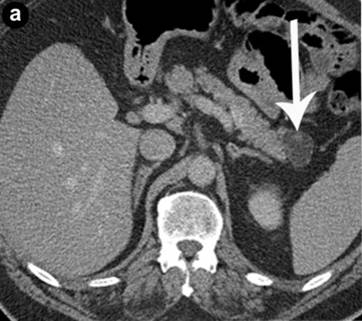

Various radiologic investigations were used in the pre-operative evaluation of the lesions. Imaging studies included CT scans, MRI and endoscopic ultrasound (EUS). All lesions were exophytic with one cyst originating from the head of the pancreas, two from the body, and three from the tail region. One patient had papillary projections into the lesion. Multiphase enhanced CT scan of the abdomen typically revealed a well-defined hypodense mass with imperceptible walls and Hounsfield units in the range of 15-20 (Figures 1 and 2). MRI of the abdomen was performed in one case and again showed a well-circumscribed exophytic lesion of the body of the pancreas with high T1 signal intensity, intermediate T2 signal intensity, with no enhancement following intravenous contrast administration (Figure 3). magnetic resonance cholangiopancreatography (MRCP) sequences did not show any continuity with the ductal system.

Figure 2. A 63-year-old male being worked up for a pancreatic mass (Case #4). Axial (a.) and sagittal (b.) venous phase CT show a well defined pancreatic tail mass measuring approximately fluid attenuation, with an enhancing mural nodule (arrowhead). |